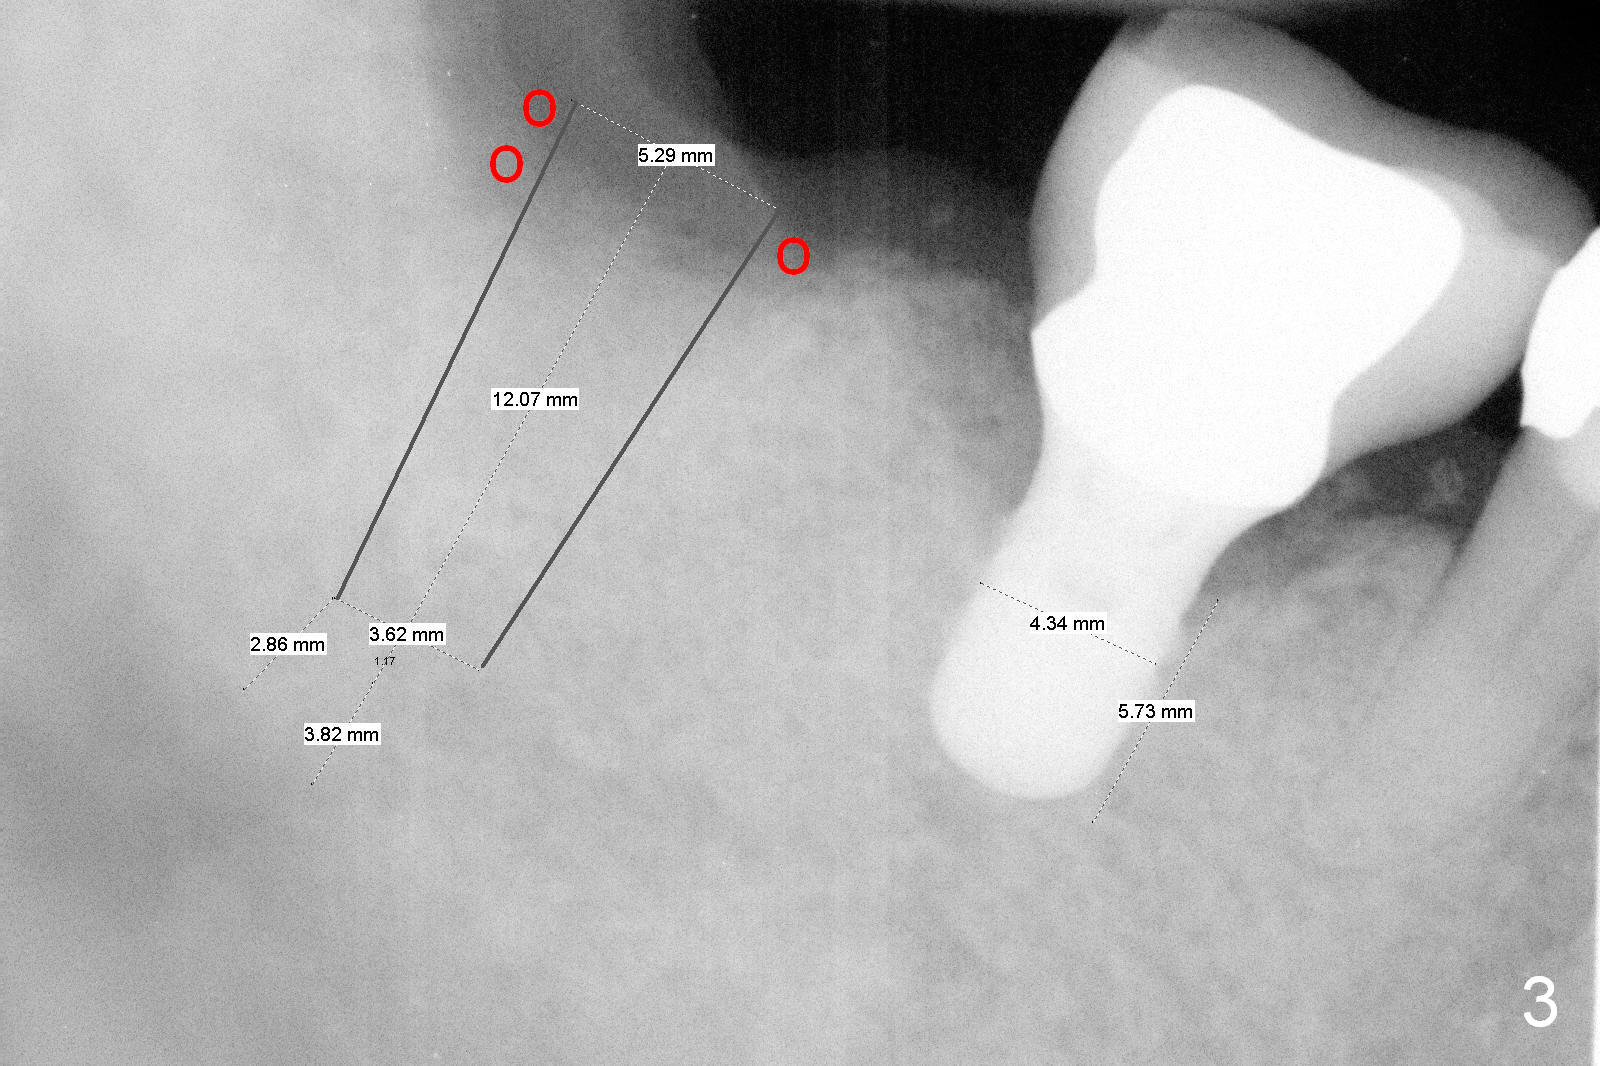

Fig.3 is a design to place a 5.3x12 bone level implant in the middle of the healing socket. The drawbacks are two folded. First the implant is placed too distally. Second, the implant is close to the underlying nerve.

No matter which design, there is possibility of the buccal threads of the implant. Bone graft is expected. Collagen dressing should be cut in a ring shape, fixed by an abutment.